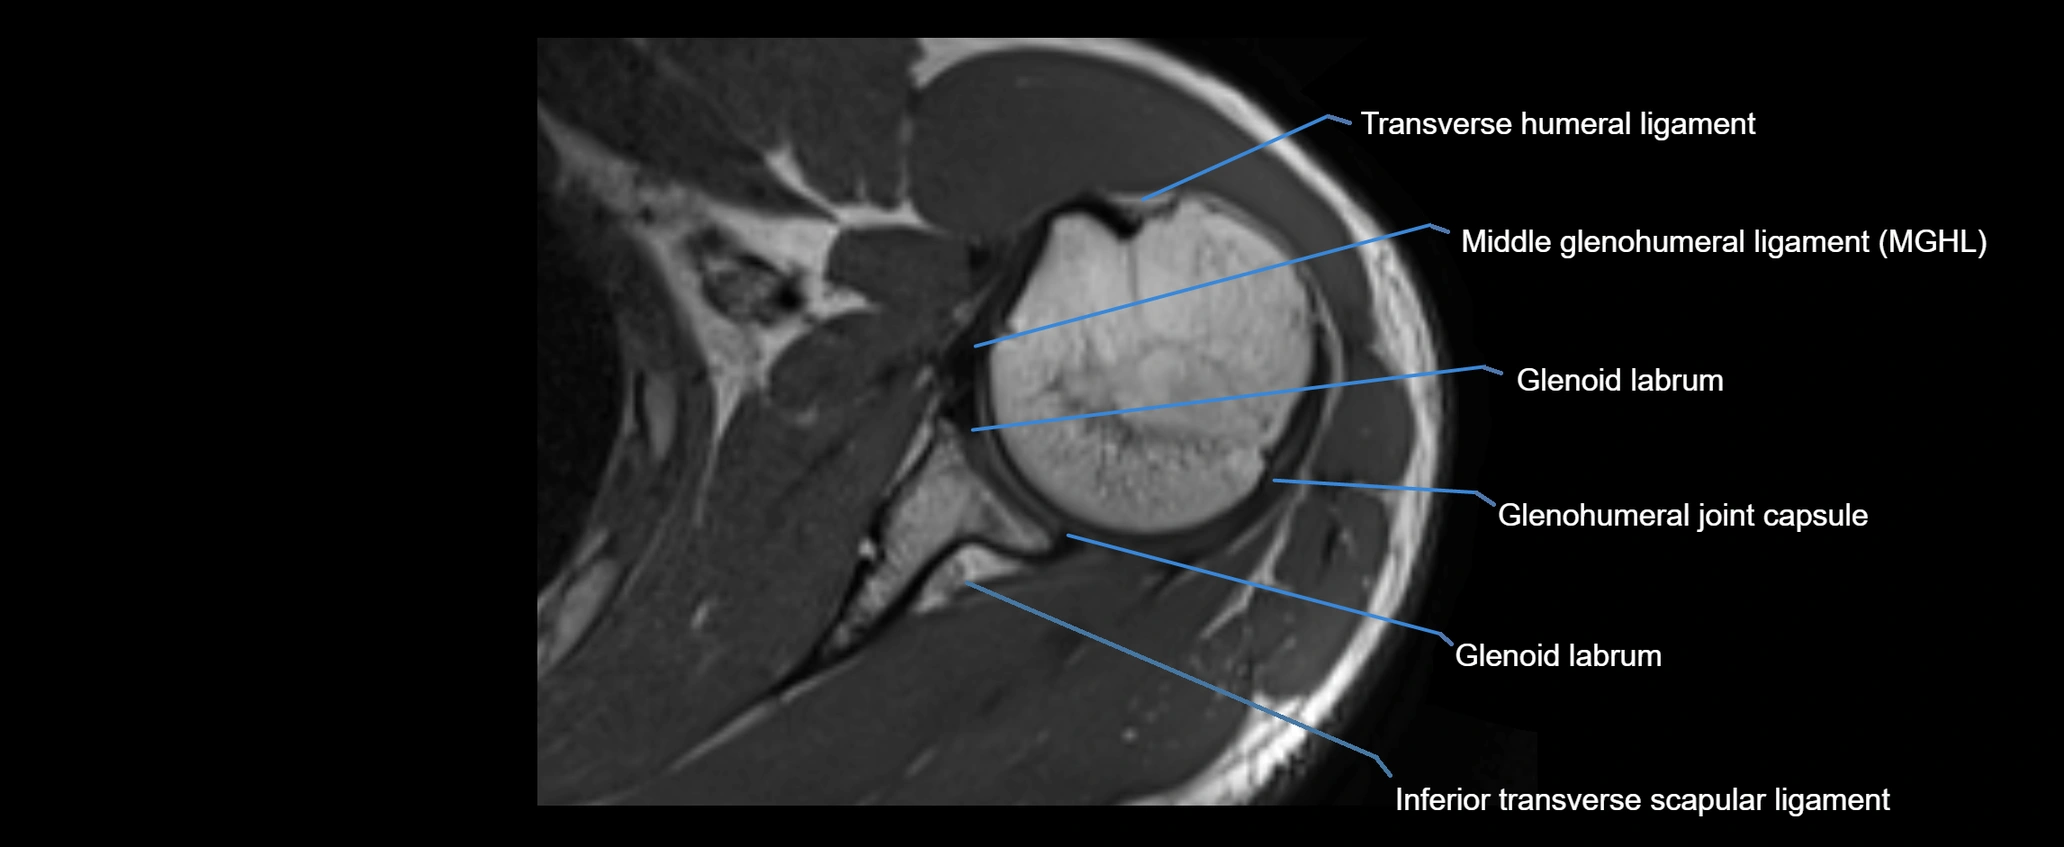

MRI images

image